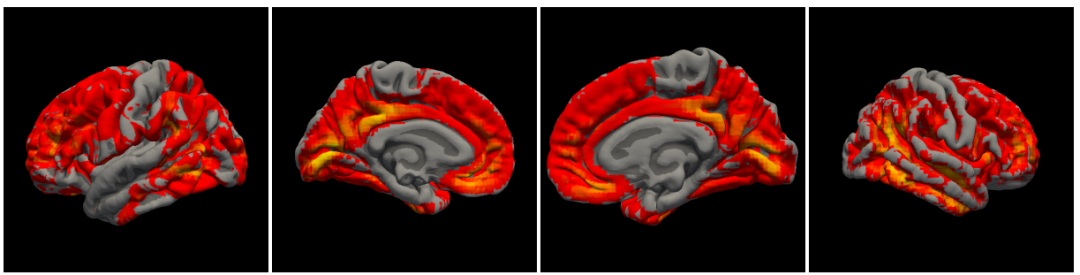

除了把ROI变换到数据空间,然后提取数据。是否可以把数据变换到ROI所在空间,进行提取呢?尝试了一下将MIN152空间的group level的数据变换到fsaverage空间,用的命令同样是mri_vol2surf。过程中如果出现voxel size的warnning可用3dresample可以解决。

不过效果一般,至少直接在group level上做是不好的。理想的做法是先在个体上做变换,然后得到在surface上操作得到group level的结果,应该就能得到比较好的coverage。